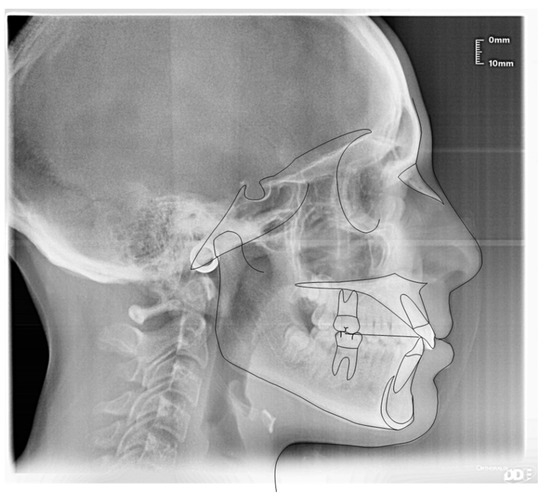

3.1. Clinical Case #1

3.2. Clinical Case #2

3.3. Clinical Case #3

3.4. Clinical Case #4